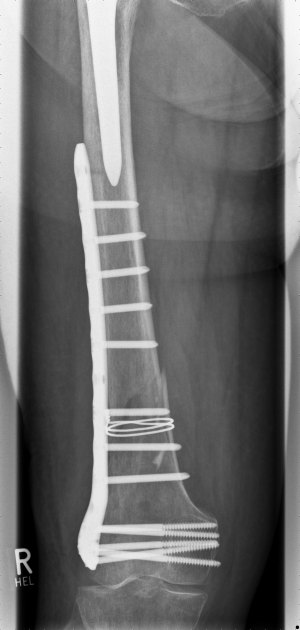

This 81 year old patient suffered from a Vancouver C; OTA 33 A1 fracture pattern.

The fracture was reduced and fixed in a mini open technique by cerclage and an NCB Distal Femur plate. In the presented case the plate could have been longer in order to overlap the stem of the hip prosthesis at minimum 3-4 cm. Nevertheless the fracture healed uneventfully.